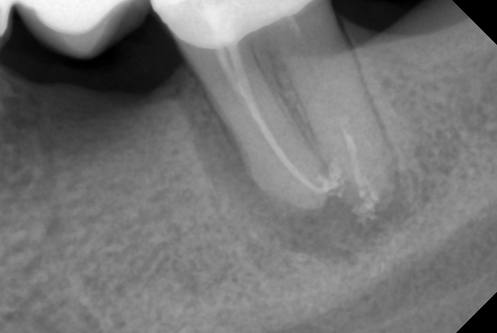

В стоматологической клинике "5 Принципов" в Симферополе мы гордимся тем, что каждый пациент получает индивидуальный подход и безупречный результат в области эндодонтического лечения под микроскопом. Наши специалисты применяют современные цифровые технологии, микропроцессорные и нейромодуляционные инструменты, что позволяет достичь максимальной точности и минимального дискомфорта. В портфолио клиники — широкий спектр кейсов: от первичной диагностики пульпита до сложной ретенированной резорбции и повторной эндодонтии. Мы беремся за зубы любых степеней сложности: от моляра до резцов, используя щадящие концевые инструменты и безболезненные методы постоянной анестезии. Все процедуры проходят под увеличением, что обеспечивает точное удаление инфицированной ткани и сохранение естественной анатомии зуба.Особое внимание мы уделяем постпроцедурному наблюдению: контроль за герметичностью заполнения корневых каналов, профилактические рекомендации и возможная корректировка плана лечения при необходимости. В "5 Принципах" мы разумно сочетаем комфорт, эстетическую привлекательность и долгосрочную функциональность. Результат — здоровые зубы, уверенная улыбка и спокойствие наших пациентов в Симферополе. Запишитесь на консультацию и убедитесь сами в нашем подходе к качественному эндодонтическому лечению.